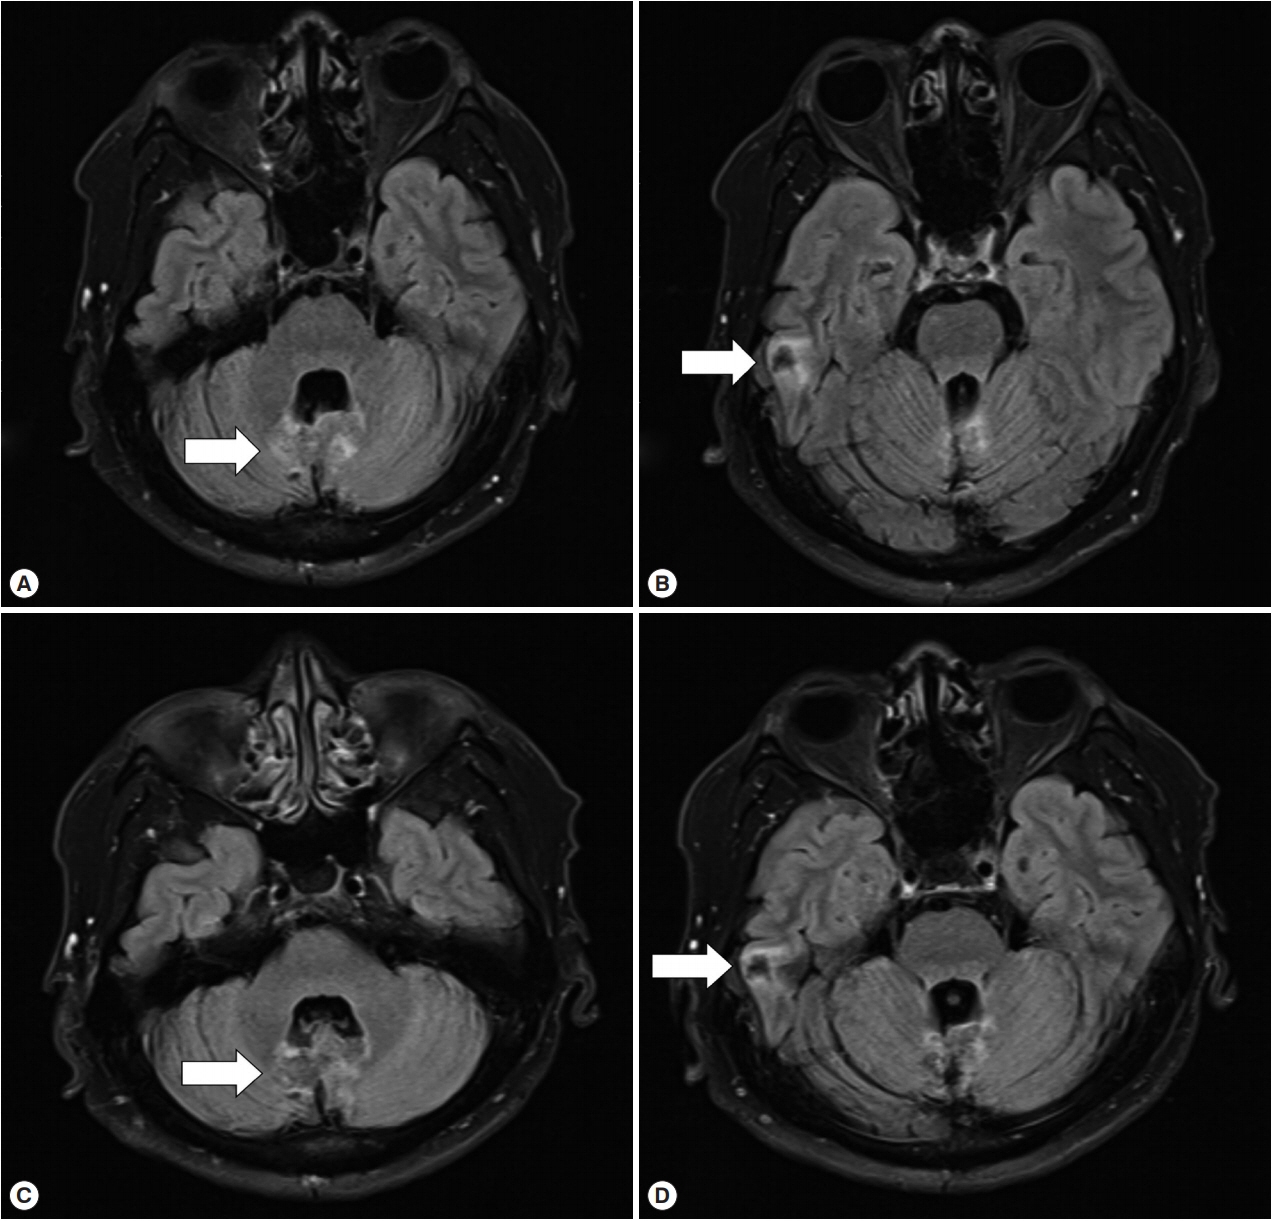

A 53-year-old businessman visited our hospital due to worsening dizziness and dysarthria starting 2 years ago. He had frequently traveled to China, Russia, and Kazakhstan between 2001 and 2007. He was previously healthy except for a history of tuberculous pleurisy 30 years ago. He was first diagnosed with a liver cyst (unknown size) by screening abdominal ultrasonography in a hospital in 2011. However, he did not follow up on the lesion. In April 2017, he visited another hospital because of non-whirling dizziness and dysarthria for several months. A 2 cm cerebellar mass and an 11.8 cm liver cyst were found in the brain magnetic resonance imaging (MRI) and abdomen computed tomography (CT), respectively (Fig. 1A, B). A stereotactic brain biopsy was attempted because a glioblastoma was suspected radiologically, but no tissue was obtained because of dense calcification. Craniotomy and mass removal were performed, and the pathologic exam revealed necrotizing granulomatous inflammation with hyalinized bodies indicating parasitic infection, although no definite parasites were found. The presumptive diagnosis was neurocysticercosis, due to the positive result from the enzyme-linked immunosorbent assay (ELISA) for cysticercosis IgG (an unknown value). The patient took albendazole, 500 mg twice a day (14 mg/kg/day), for 52 days but his dizziness did not disappear. However, he did not visit the hospital of his own will.

Fig. 1

Cystic lesions in the liver and cerebellum in 2017. (A) MRI T2 sequencing showed a 2 cm peripheral enhancing mass (arrow) in the cerebellum. (B) Liver CT, with portal vein enhancement, showed an 11 cm lobulated mass (arrow) in the right posterior section of the liver.

Fig. 1 Cystic lesions in the liver and cerebellum in 2017. (A) MRI T2 sequencing showed a 2 cm peripheral enhancing mass (arrow) in the cerebellum. (B) Liver CT, with portal vein enhancement, showed an 11 cm lobulated mass (arrow) in the right posterior section of the liver.